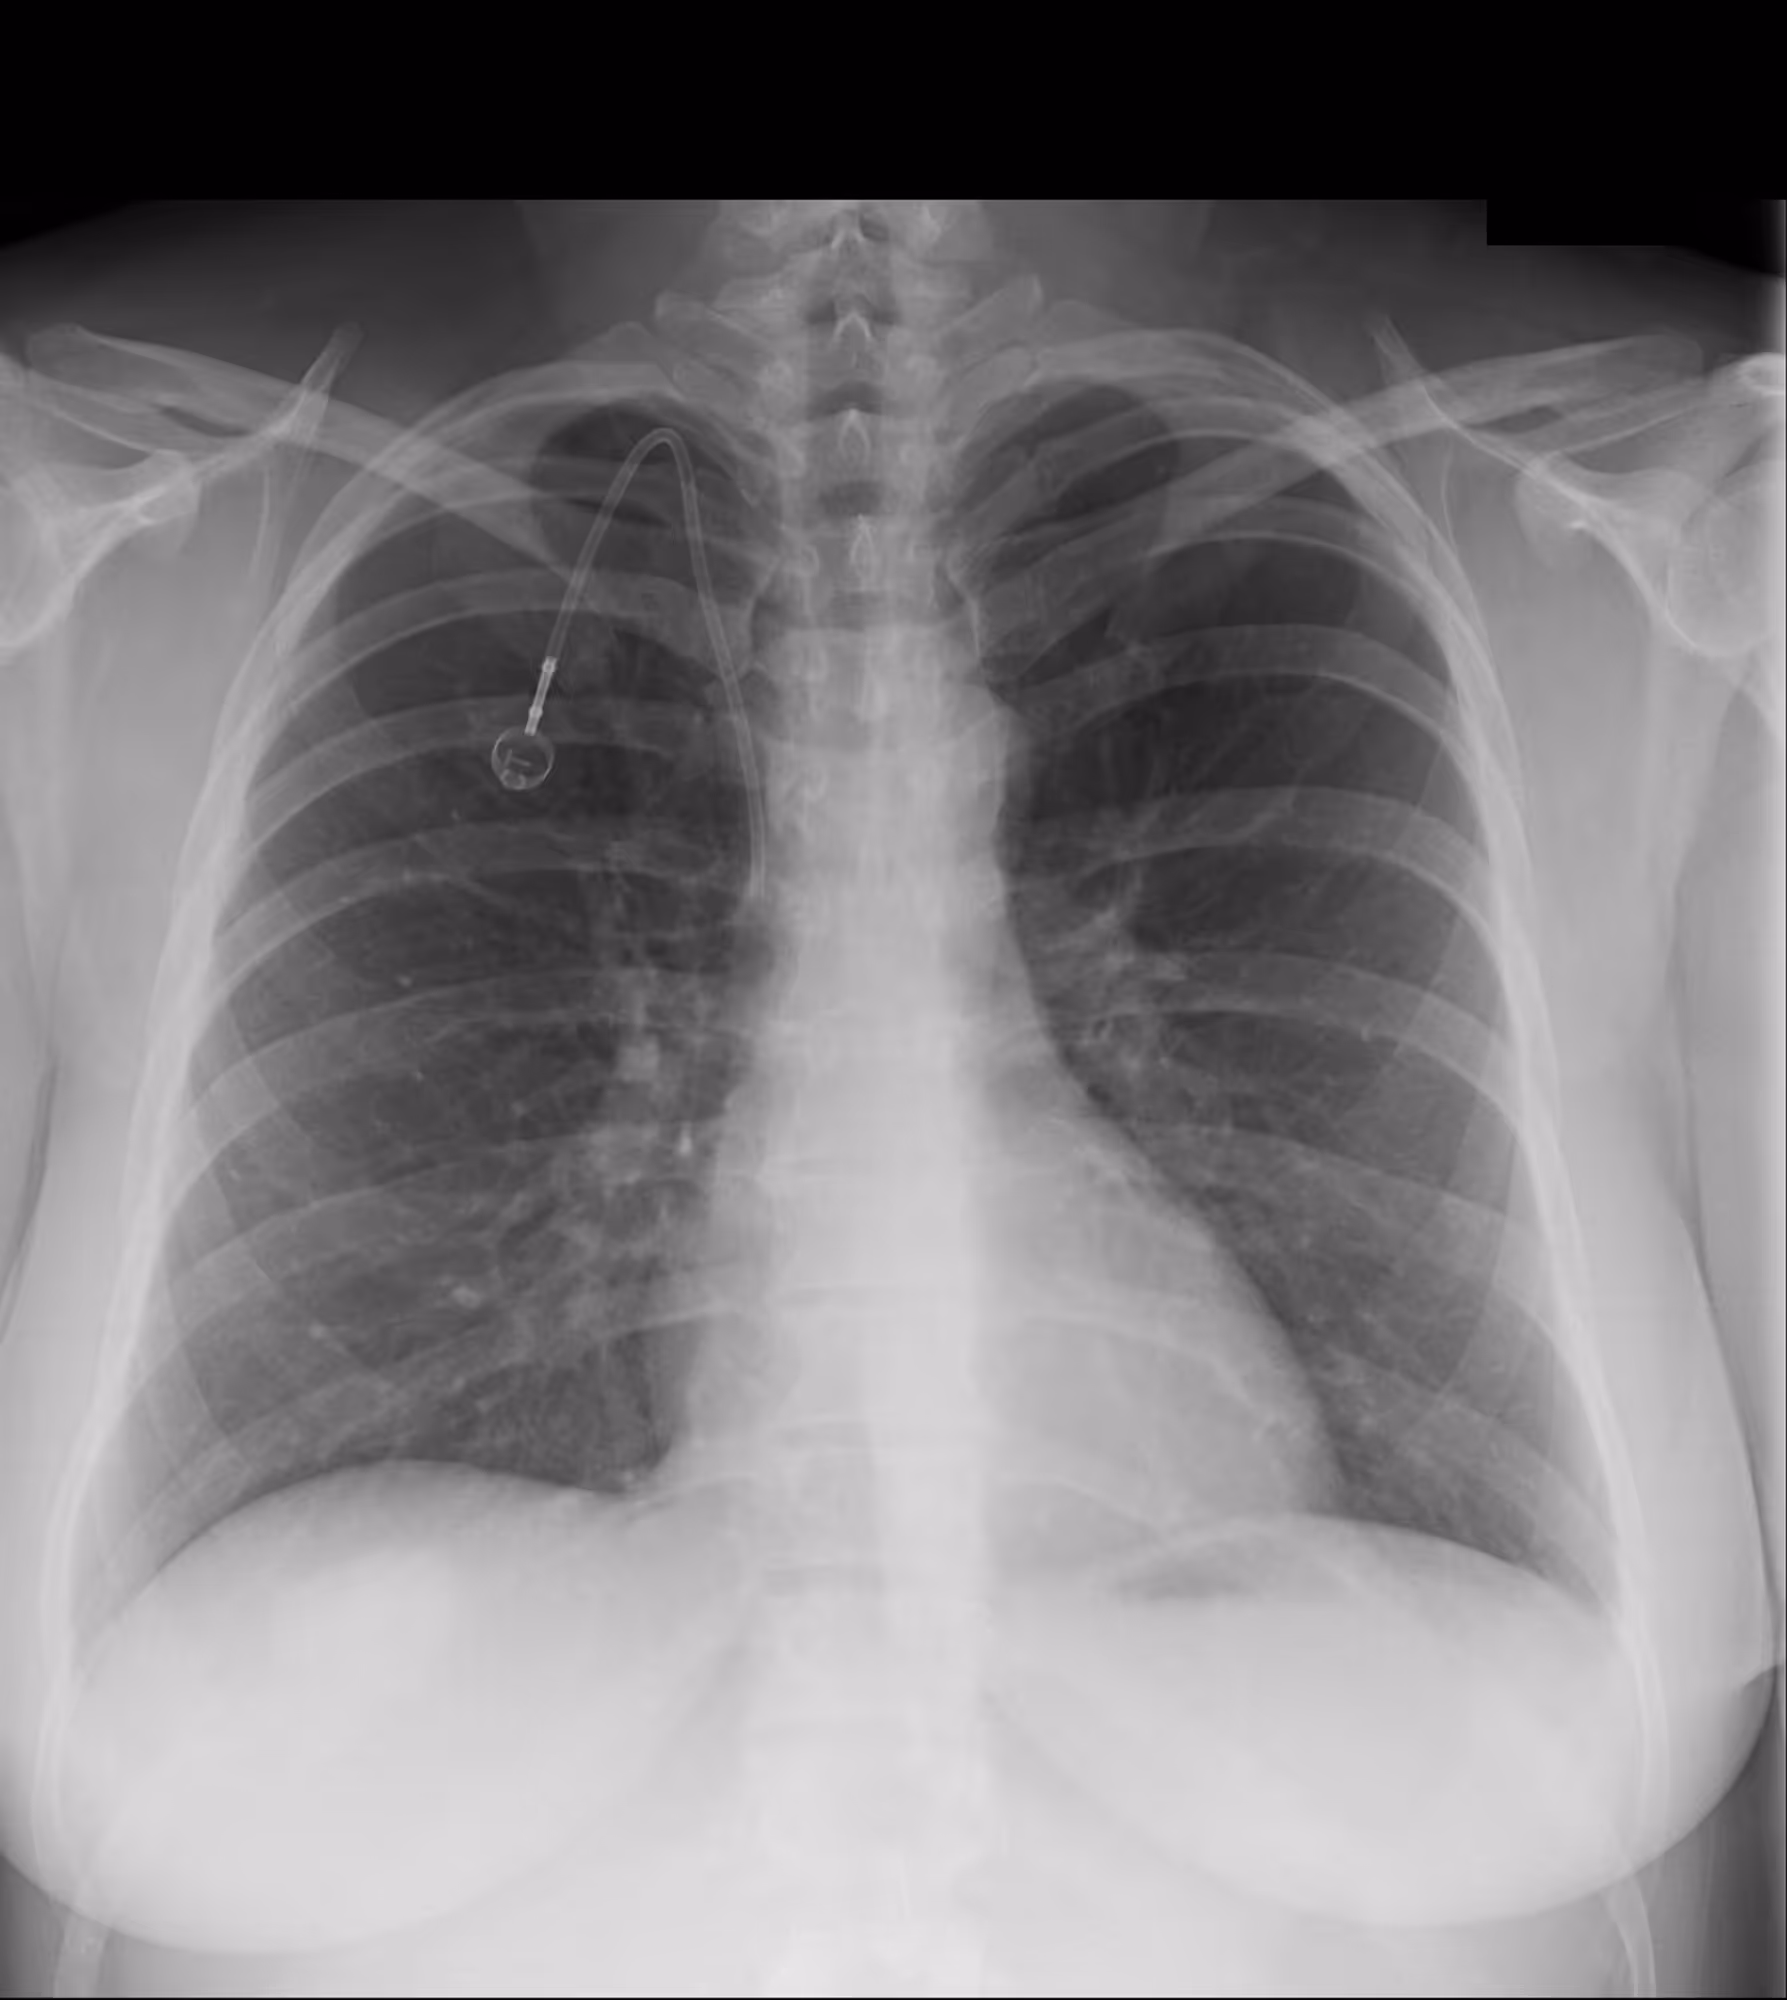

Indication

A 40-year-old female with a history of colon cancer presents for a control radiograph following biopsy of a right lower-lobe pulmonary nodule.

Results

ChestView detected a pneumothorax post-biopsy.